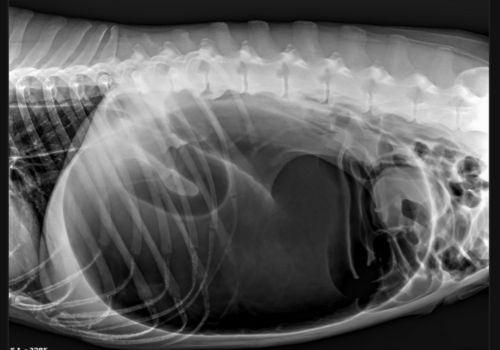

Initial evaluation of a GDV patient commonly includes emergent abdominal x-rays (radiographs) and bloodwork. An ECG (electrocardiogram) will often be used to monitor your dog's heart for abnormalities since GDV progressively impacts the patient's circulatory system. The striking radiographic abnormalities often lead to a definitive diagnosis, so subsequent interventions can be taken immediately.